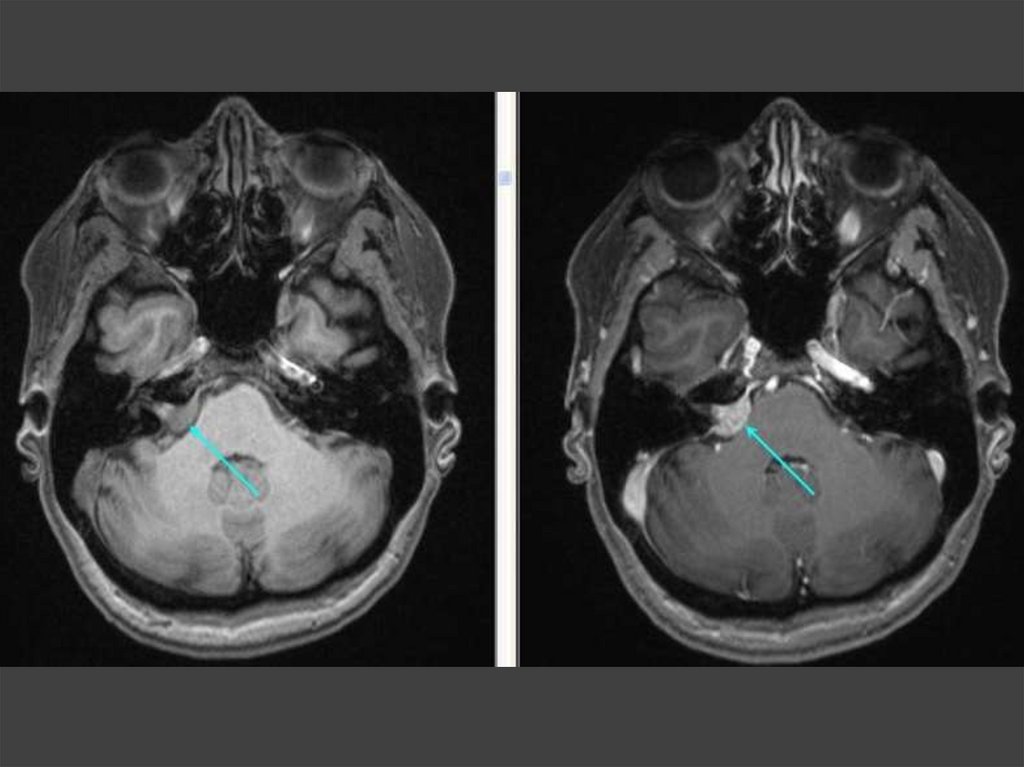

Вазоневральный конфликт

70. Холестеатома, абсцесс мозга

1

Петля верхней мозжечковой

артерии пролабирует во

внутренний слуховой проход и

соприкасается с вестибулокохлеарным нервом